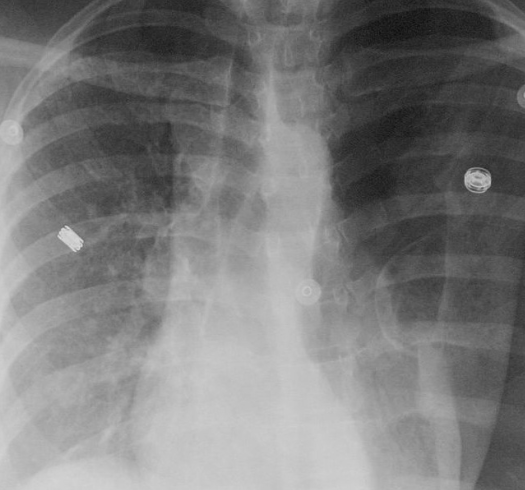

기흉이 심해지면 흉막강 내 공기가 계속 축적되어 폐와 심장을 압박하는 긴장성 기흉이 발생할 수 있는데, 이 상태는 생명을 위협하는 응급상황으로 혈압 저하, 청색증, 의식 저하 등이 나타나며 즉각적인 응급조치가 필요합니다. 진단 방법은 보통 흉부 X선 촬영으로, 허탈된 폐와 흉막강 내 공기를 확인하며, 더 정밀한 원인 분석과 확진을 위해 흉부 CT를 시행하기도 합니다. 청진 시에는 기흉이 있는 쪽 가슴에서 호흡음이 감소하거나 사라진 점도 진단에 도움이 됩니다.

하지만 기흉의 크기가 크거나 호흡곤란과 같은 증상이 심하면 흉관 삽입술이 필요합니다. 이 방법은 늑골 사이로 특수한 플라스틱 관인 흉관을 삽입해 흉막 공간에 있는 공기를 밖으로 빼내 폐를 재팽창시키는 치료법으로, 지속적인 공기 누출이 있거나 재발성이 강한 경우에 매우 효과적입니다. 흉관 삽입은 대개 국소마취 하에 진행되며 필요에 따라 흡인장치를 사용해 치료 효과를 높입니다.